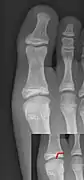

Salter–Harris fracture types

There are nine types of Salter–Harris fractures; types I to V were originally described,[3] and types VI to IX were added subsequently:[5]

• Type I – transverse fracture through the growth plate (also referred to as the "physis"):[6] 6% incidence

• Type II – A fracture through the growth plate and the metaphysis, sparing the epiphysis:[7] 75% incidence, takes approximately 12-90 weeks or more in the spine to heal.[8]

• Type III – A fracture through growth plate and epiphysis, sparing the metaphysis:[9] 8% incidence

• Type IV – A fracture through all three elements of the bone, the growth plate, metaphysis, and epiphysis:[10] 10% incidence

• Type V – A compression fracture of the growth plate (resulting in a decrease in the perceived space between the epiphysis and metaphysis on x-ray):[11] 1% incidence